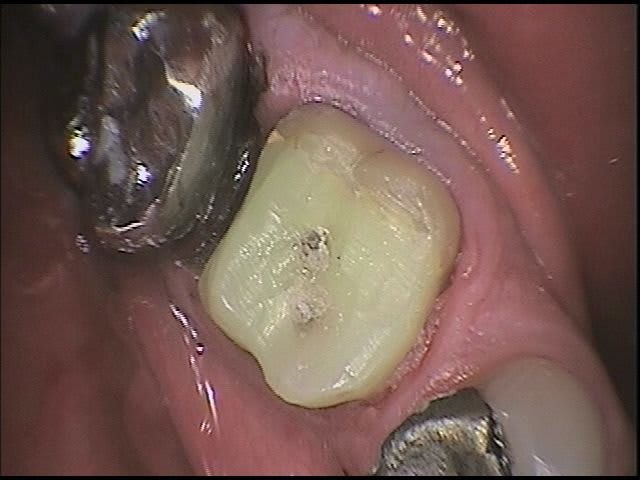

Ps je ne vois pas ce que vous trouvez de particulier à ma technique formes, heu visio form.